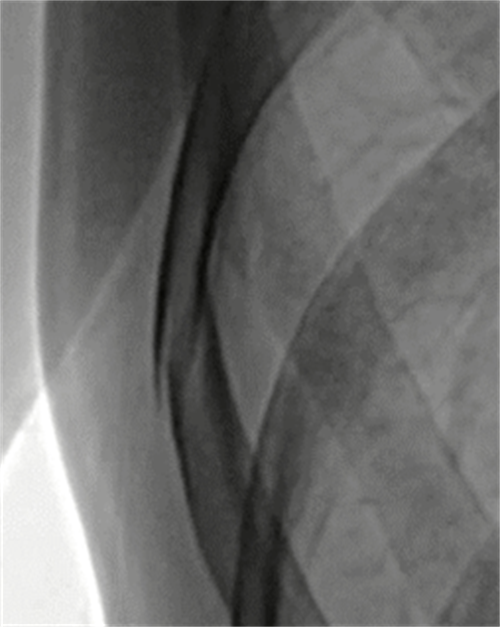

从功能方面上,动态DR是一款多功能DR,可以进行数字化x线摄影、数字化x线造影、数字化x线透视等,相较于静态DR,动态DR具备更多的临床应用场景。;从技术方面:动态DR是使用多功能动态数字探测器成像的直接数字化X射线摄影系统;从临床方面:动态DR具有(17inch×17inch)高清拍片、大幅面(17inch×17inch)透视、毫秒级高清点片、可视化造影、全身拼接、视频实时保存回放等支持精准诊断的功能。(第一张图为动态DR诊断隐匿性病灶临床图像,第二张图像为上消化道造影图像)